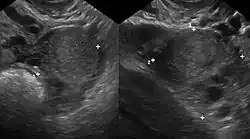

Durch eine transvaginale Ultraschalluntersuchung können große Endometrioseherde entdeckt werden. Bei Verdacht auf einen Befall des Enddarms kann eine zusätzliche transrektale Ultraschalluntersuchung hilfreich sein. Zur Klärung der Ausdehnung einer tiefen infiltrierenden Endometriose kann in Einzelfällen eine Magnetresonanztomographie beitragen. Die Krankheit kann dadurch aber bei negativem Befund der bildgebenden Verfahren nicht ausgeschlossen werden.[10]